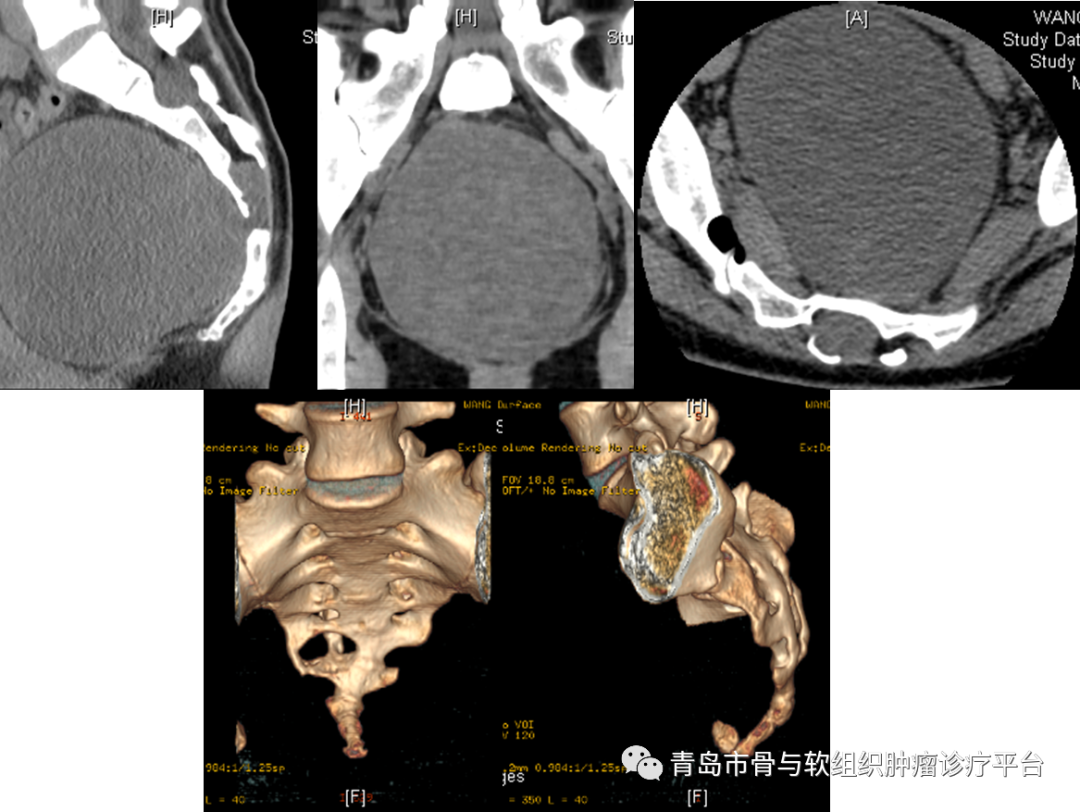

病例簡介患者王某某,女性,27歲。主訴:發(fā)現(xiàn)骶尾部腫物4月余?,F(xiàn)病史:發(fā)現(xiàn)骶尾部腫物4月余,無疼痛不適,大小便功能正常,會陰區(qū)無明顯麻木不適。外院行骶尾部MR示:骶管內(nèi)及骶椎前占位,脊索瘤?神經(jīng)源性腫瘤?為求進(jìn)一步治療就診于我院,門診以“骶尾部腫物”收治入院,患者自患病以來,精神可,飲食睡眠可,大小便未見明顯異常,體重未見明顯變化。查體:雙下肢活動及感覺可,雙側(cè)伸髖、屈髖、伸膝、屈膝活動可。骶尾部無明顯壓痛、叩擊痛,會陰區(qū)無明顯麻木不適。目前診斷:骶尾部占位性病變術(shù)前檢查術(shù)前骶尾部T2相MRI平掃術(shù)前骶尾部MRI增強(qiáng)平掃術(shù)前骶尾部CT三維成像術(shù)前討論1.?骶前巨大腫瘤,考慮為脊索瘤或神經(jīng)鞘瘤可能大。切除過程中使用超聲骨刀行骶骨截骨,有效降低術(shù)中出血風(fēng)險(xiǎn)。2.?術(shù)中需要充分保護(hù)雙側(cè)S3神經(jīng)根,降低術(shù)后患者出現(xiàn)大小便功能異常的風(fēng)險(xiǎn)。術(shù)后關(guān)注患者大小便功能,早期康復(fù)鍛煉。3.?骶前區(qū)有一層松散的組織,盡量使用鈍性分離直腸,避免出現(xiàn)不必要的損傷。4.手術(shù)切除后存在較大空腔,感染風(fēng)險(xiǎn)較大。術(shù)前需要進(jìn)行預(yù)防性使用抗生素,術(shù)前12h行清潔灌腸。術(shù)后關(guān)注引流情況。手術(shù)過程術(shù)后病理肉眼所見:灰白結(jié)節(jié)樣物一枚,帶部分骨組織,結(jié)節(jié)大小1110.79.5cm,距骨斷端1.5cm,骨組織大小107.22cm,切面灰白灰黃質(zhì)稍韌,部分呈膠凍樣,包膜完整。病理診斷:(骶骨腫瘤)神經(jīng)鞘瘤(大小1110.79.5cm),部分區(qū)域水腫、退變,局灶區(qū)域邊界欠清,侵及骨組織,建議密切隨訪復(fù)查。免疫組化結(jié)果:S-100(+),SOX10(+),CK(-),Brachyury(-),H3K27Me3(+,表達(dá)未缺失),Ki-67(+,2%),Desmin(-),INI-1(+,表達(dá)未缺失),CD34(部分+),EMA(-)。病例總結(jié)涉及骶骨的腫瘤主要包括原發(fā)性和轉(zhuǎn)移性腫瘤。轉(zhuǎn)移性腫瘤較原發(fā)性腫瘤更常見。最常見的良性骶骨腫瘤是巨細(xì)胞瘤。最常見的原發(fā)性骶骨惡性腫瘤是脊索瘤,其次是軟骨肉瘤。神經(jīng)鞘瘤起源于神經(jīng),但其臨床上與其他骶骨腫瘤類似,治療方法也相同,被歸類為骶骨腫瘤。骶骨是神經(jīng)源性腫瘤的好發(fā)部位之一,絕大多數(shù)為良性周圍神經(jīng)鞘瘤。術(shù)前完善的影像學(xué)檢查和實(shí)驗(yàn)室檢查十分必要。被忽視的周圍神經(jīng)鞘瘤后期可能發(fā)展到非常巨大,導(dǎo)致盆腔器官功能障礙。大多數(shù)良性周圍神經(jīng)鞘瘤可以接受保留功能的保守手術(shù)切除治療。需要密切關(guān)注腫瘤復(fù)發(fā)情況,必要時(shí)進(jìn)行大劑量放療控制腫瘤生長。對于惡性周圍神經(jīng)鞘瘤,多由神經(jīng)纖維瘤病惡化而來。治療方法包括放療和整塊手術(shù)切除。慢性神經(jīng)壓迫引起的慢性、鈍性、下背部或尾部疼痛是骶骨腫瘤最常見的癥狀之一。腫瘤壓迫可能導(dǎo)致腸道或泌尿系統(tǒng)習(xí)慣改變。骶骨下段腫瘤體積足夠大時(shí),直腸指診可以觸及其前部。對于較大的骶骨腫瘤,如脊索瘤和軟骨肉瘤,臀部可能出現(xiàn)巨大腫塊。高度惡性腫瘤的患者劇烈疼痛可能持續(xù)數(shù)周,行走困難,出現(xiàn)強(qiáng)迫體位等。骶骨腫瘤外科手術(shù)前需要完善影像學(xué)檢查:包括平片、CT、MRI、血管造影。必要時(shí)PET-CT檢查。術(shù)前需要明確切除范圍,精準(zhǔn)切除,盡可能多保留骶神經(jīng),以降低術(shù)后出現(xiàn)大小便功能異常的風(fēng)險(xiǎn)。Todd等研究證實(shí),雙側(cè)S3神經(jīng)保留的患者中,正常的腸和膀胱功能分別保持在100%和69%。骶骨手術(shù)術(shù)后出現(xiàn)的并發(fā)癥包括:術(shù)中失血、感染、傷口問題(包括切口感染、皮膚或肌肉壞死、傷口愈合不良等)、直腸損傷、神經(jīng)損傷(腫瘤較大時(shí)需關(guān)注坐骨神經(jīng))、腦脊液漏等。因此術(shù)前需要進(jìn)行根據(jù)腫瘤范圍大小,考慮術(shù)前12-24h行動脈栓塞或球囊植入,降低出血風(fēng)險(xiǎn)。術(shù)中可行控制性降壓和控制性低溫,以減少術(shù)中出血。術(shù)前24h預(yù)防性使用抗生素,術(shù)前12h行清潔灌腸,降低術(shù)后感染風(fēng)險(xiǎn)。近年來,青大附院骨腫瘤團(tuán)隊(duì)目前已常規(guī)開展各類骶骨腫瘤切除手術(shù),大多數(shù)患者圍手術(shù)期出血少,術(shù)后預(yù)后良好,目前也已經(jīng)成為我科特色診療技術(shù)之一。